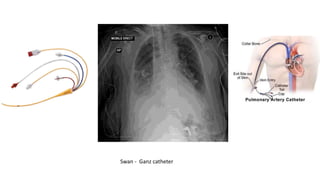

Placement of central lines.

• Swan - Ganz catheter is correctly placed when its tip lies in the right

or left pulmonary artery. Catheter measure cardiac output and heart

pressure. Inserted through subclavian , jugular or femoral vein .

• Make sure to position patient and tube correctly in order to show

correct placement of catheter in radiograph .

• Avoid patient rotation .

Swan - Ganz catheter